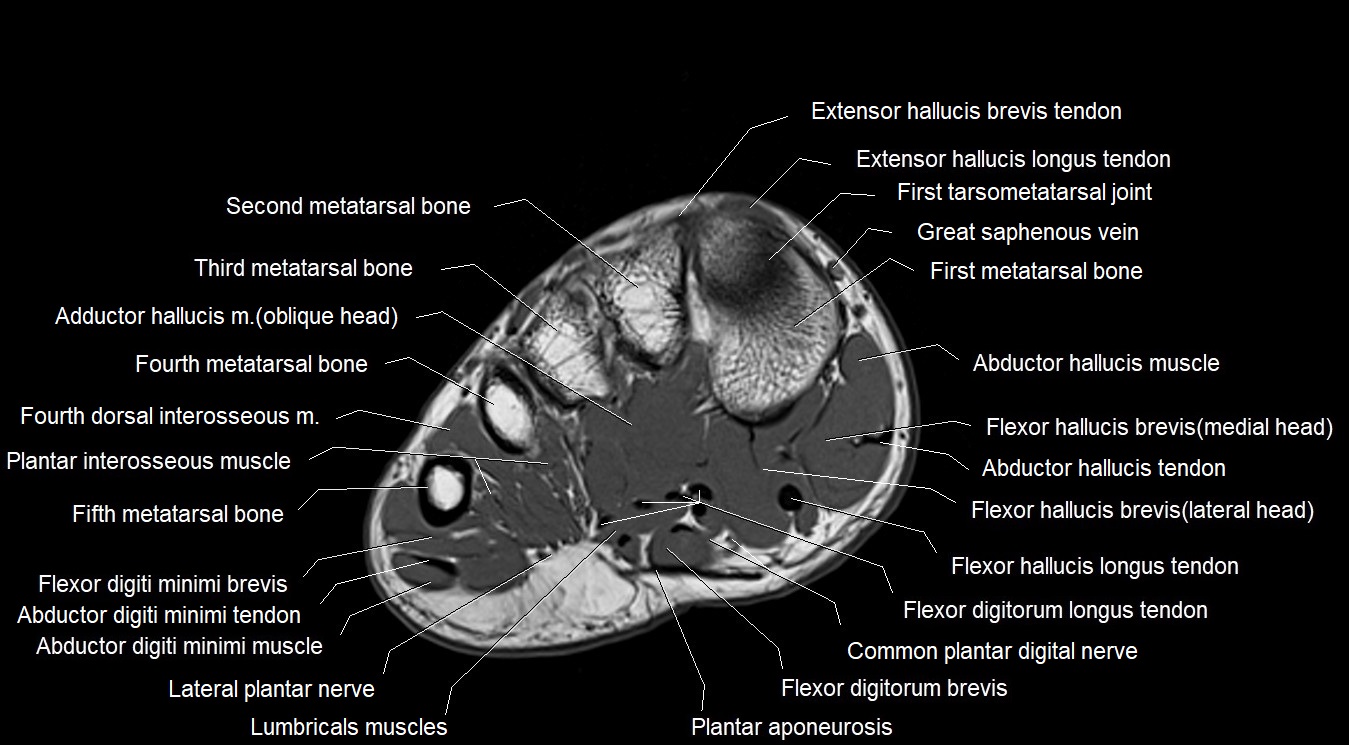

MRI image